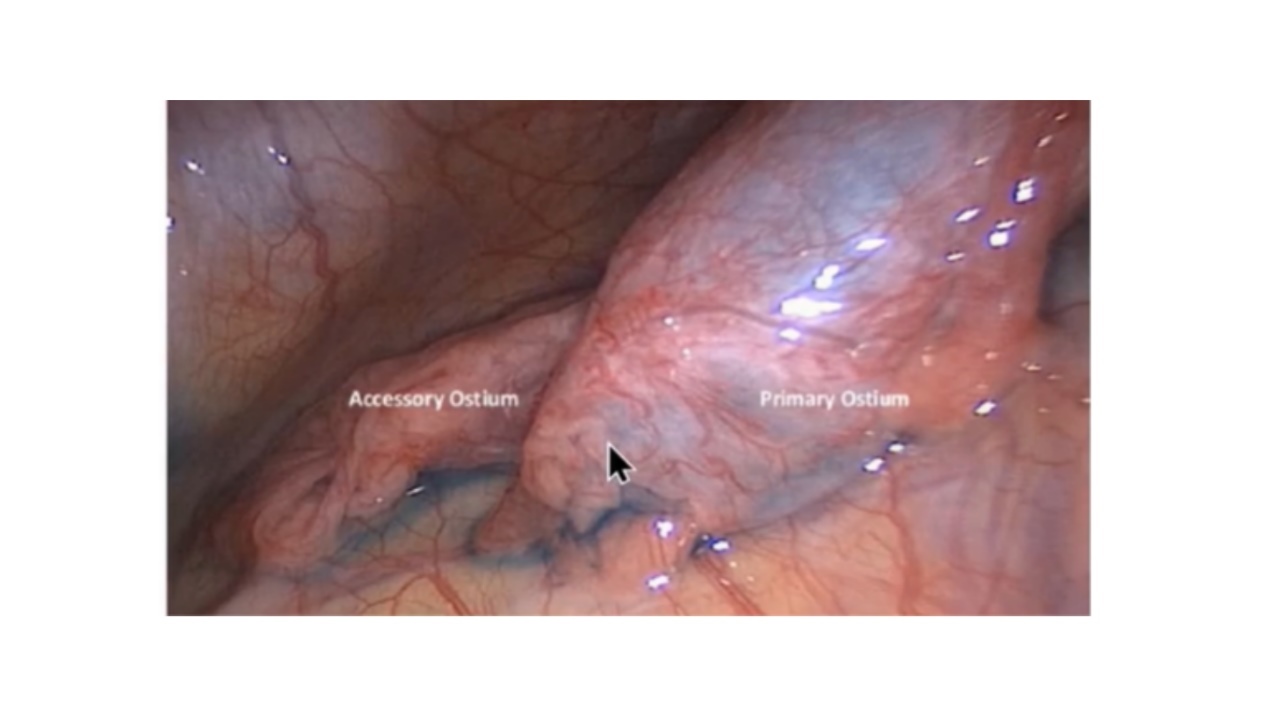

腹腔镜图中可见右输卵管有两个独立的输卵管开口,即主口和副口。